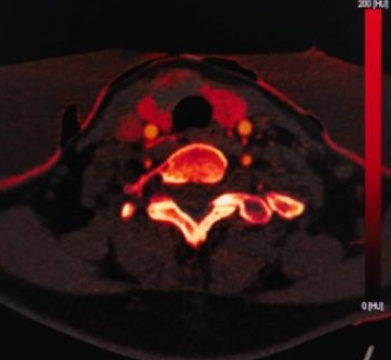

(a) (b) (c) (d)

(a)~(d)甲状腺滤泡性腺瘤患者双能量CT增强扫描动脉期原始图像、碘图、Rho/Z图及病理图

Figure 1. Examples of dual-energy CT arterial phase images, iodine uptake images, Rho/Z images, and pathological findings in three groups of patients with thyroid nodules (HE, ×100, H) (Rho/Z, Electron Density/Effective Atomic Number)

1. 三组甲状腺结节患者双能量CT动脉期图、碘图、Rho/Z图及病理图示例(HE, ×100, H) (Rho/Z,电子密度云/有效原子序数)